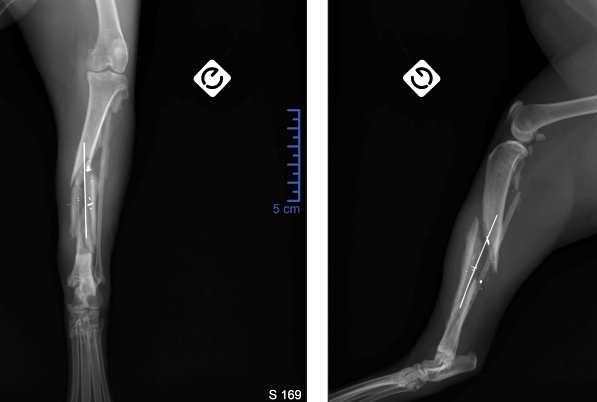

14 jours post-opératoires, des radiographies sont faites et montrent une instabilité du montage, une dé réduction ainsi qu’une fracture de la fibula, initialement intacte (figure 3). Il est référé 3 jours plus tard à la clinique Alvetia pour gestion du cas avec possible reprise chirurgicale.

Figure 3 : Dégradation de la réduction, 14 jours post-opératoires